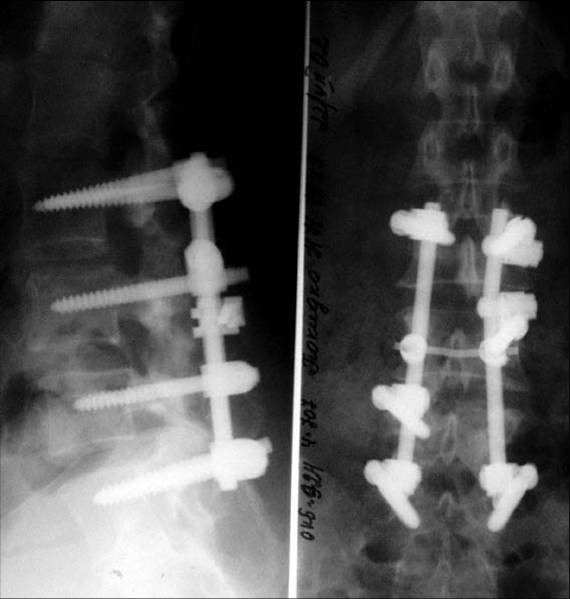

- Консервативное и оперативное лечение пациентов с дегенеративно-дистрофическими повреждениями позвоночных сегментов (остеохондроз, спондилез, спондилоартроз, грыжи и протрузии дисков), как современными транспедикулярными фиксаторами, пластинами для передней фиксации, так и динамическими системами - практически не ограничивающими физиологический объем движений;

- Оперативное и консервативное (ортезирование, корсетирование) лечение переломов и посттравматических деформаций ( в т.ч. неправильно срастающихся переломов, клиновидных деформаций, спондилопатий) с использованием систем, позволяющих при минимальной инвазивности добиться отличной реконструкции и восстановления;

- Лечение пациентов с врожденными и приобретенными деформациями позвоночника (болезнь Шойерманна, клиновидные позвонки, спондилолиз, спондилолистез, спондилоптоз),